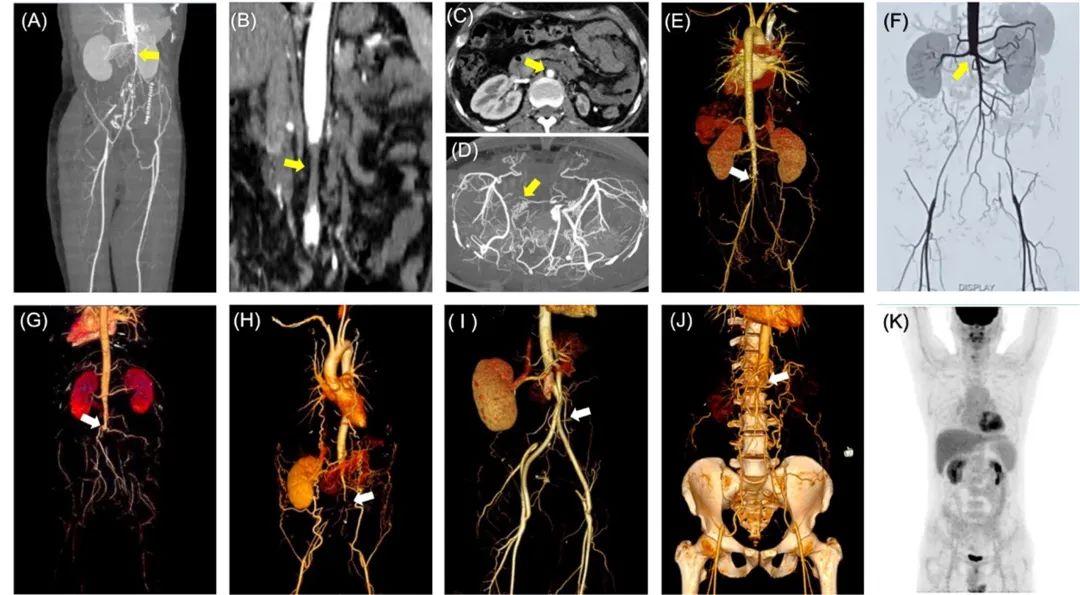

12例CAAOD患者的腹主动脉病变程度各异,包含1例轻度狭窄,3例中度狭窄和8例完全闭塞。病变范围大多起始于肾下腹主动脉,可延伸至髂总动脉,3例患者同时伴有单侧或双侧肾动脉狭窄。研究人员对其中9例患者的腹主动脉CTA影像进行测量,发现平均腹主动脉狭窄病变长达77.46mm,病变最广泛者可超过100mm;除了1例患者存在腔内继发血栓,其余患者血管最狭窄处的管壁在3、6、9、12四个点位方向的厚度基本均匀,且未见显著增厚。此外,1例患者在发病急性期完善了PET-CT评估,检查结果未见血管壁代谢升高。(图2)

图2 APS相关腹主动脉闭塞性疾病的影像学表现早期筛查CAAOD与充分治疗APS有助于预后